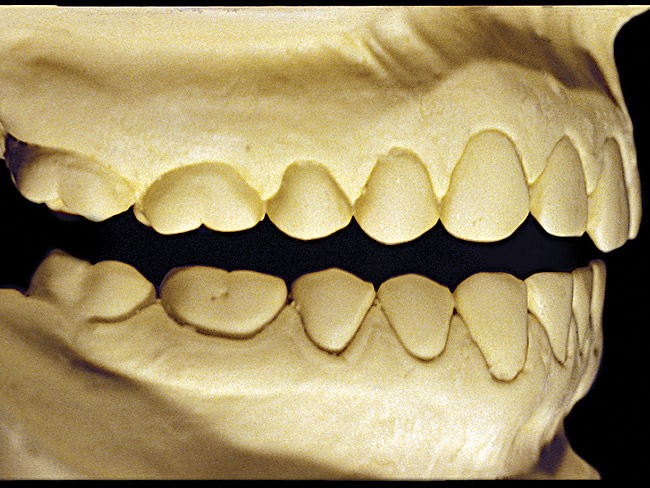

Figure 6  Moderate NCLTS from bruxism, mandibular arch.

Figure 6

The patient shown in Figure 3 and Figure 4 exhibited severe NCLTS from bruxism. Examination of the casts indicated that the NCLTS was progressively greater toward the anterior teeth. Cupping and cratering was not present because there was no secondary cause. Figure 5 and Figure 6 detail another bruxism patient, but to a lesser degree and one with cupping/cratering caused by toothpaste. The cups or craters were not caused from bruxism because the teeth could not touch the bottom of the invaginations. In both featured patients, upon hand-articulating the casts, the NCLTS facets matched up and the diagnosis of bruxism was confirmed.